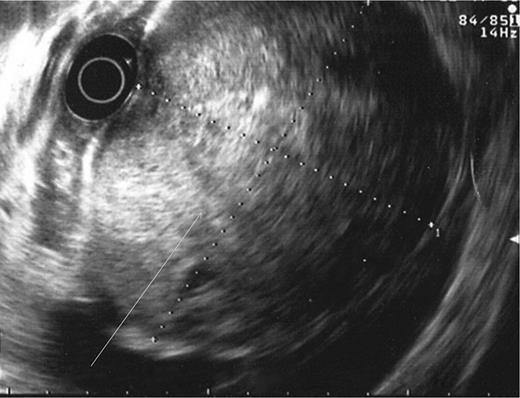

During the second day of admission, the patient passed out large amounts of melena and had an episode of haematemesis. She also developed tacchycardia with heart rate increasing to 110–120 b.p.m. Repeat blood investigations showed that haemoglobin had fallen from 6.8 to 5.3 g/dl despite blood transfusion. An emergency oesophagogastroduodenoscopy was performed. Findings were that of grade 1 oesophageal varices with no features of variceal bleed. There was a large clot in the fundus and cardia of the stomach. After attempted removal of the blood clots with flushing, the patient developed torrential bleeding necessitating intubation for airway protection. The bleeding eventually ceased spontaneously and the source of bleeding was identified to be originating from a large ulcer crater in the greater curve with an overlying clot (Fig. 1). Endoscopic ultrasound was performed which showed a 10 cm mass lesion abutting the stomach wall and extending into the peritoneal cavity (Fig. 2). The preliminary impression was that of a bleeding GI stromal tumour and care was transferred to the surgical team for consideration of surgical intervention.

Endoscopy showing ulcer crater in greater curvature of stomach.